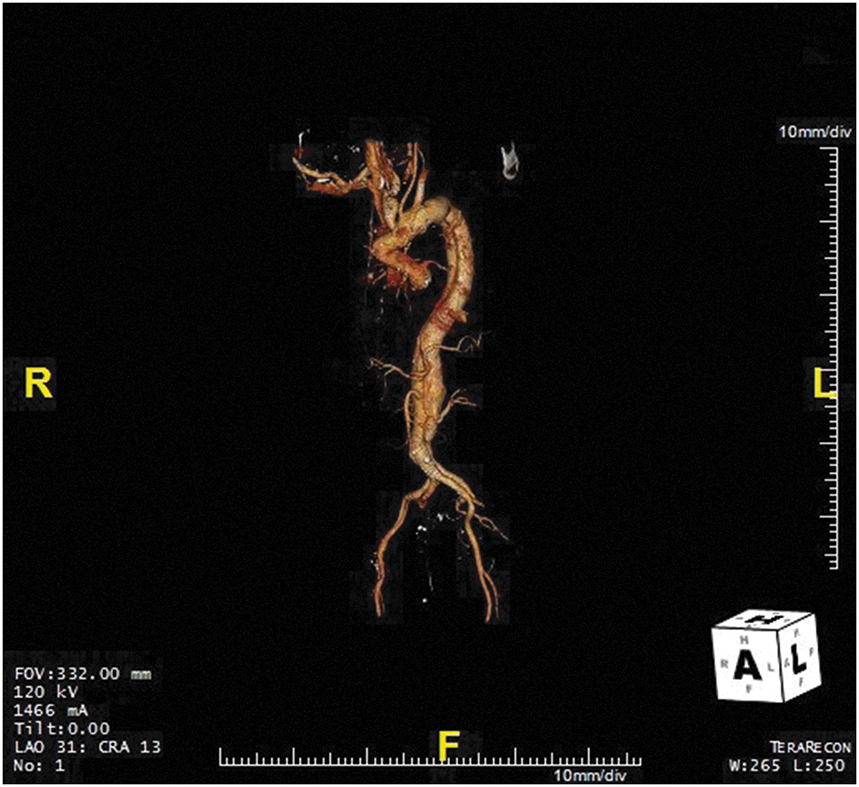

CT angiography (Figure 9.2) is the first-line imaging modality that can provide accurate measurement of the maximal diameter of the aneurysm, delineate the extent of the aneurysm, and detect branch vessel involvement and acute aortic syndromes (AASs), such as aortic dissection, intramural hematoma (IMH), or penetrating aortic ulcer. Magnetic resonance angiography (MRA) also provides high-resolution three-dimensional aortic assessment but is considered a second-line modality due to longer scan times, higher costs, and limited availability. Transthoracic echocardiography (TTE) and transesophageal echocardiography (TEE) provide assessment of aortic pathology, valvular disease, and cardiac function; TEE has a limited role in the primary assessment of TAA unless concurrent structural cardiac disease or AASs are suspected (Figure 9.3).

Figure 9.2.: Three-Dimensional (3D) Compute Tomography Reconstruction Demonstrating a Thoracoabdominal Aneurysm that Begins in the Descending Thoracic Aorta and Extends to the Infrarenal Aorta, above the Bifurcation into the Iliac Arteries.

Three-dimensional (3D) compute tomography reconstruction demonstrating a thoracoabdominal aneurysm that begins in the descending thoracic aorta and extends to the infrarenal aorta, above the bifurcation into the iliac arteries. Also seen is a chronic type B aortic dissection.